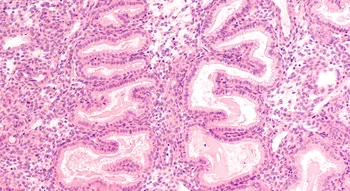

Le cycle menstruel prépare le corps féminin en vue d’une possible fécondation. Il est influencé par les hormones, dont la production est assurée par deux glandes situées dans le cerveau, l’hypothalamus et l’hypophyse, qui ordonnent au corps de libérer un ovule, aux alentours du 14e jour du cycle. En parallèle, les ovaires produisent eux aussi des hormones, les oestrogènes, responsables de la préparation d’un terrain propice à la fécondation, puisqu’ils augmentent la glaire cervicale, située juste à l’entrée du col de l’utérus. Cette glaire hébergera les spermatozoïdes qui l’atteignent, pour les libérer petit à petit, pendant 48 à 72h, vers l’ovule. Même s’ils sont des millions, un seul des spermatozoïdes va pénétrer dans l’ovule et mener à la fécondation. L’œuf peut alors commencer sa migration vers l’utérus, où les oestrogènes ont participé à épaissir l’endomètre, pour faciliter la nidification de l’embryon.